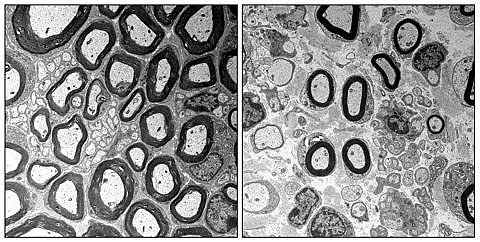

Der FAU-Arbeitsgruppe ist es nun zum ersten Mal gelungen, einen solch komplexen Zusammenhang aufzuklären. Im Mittelpunkt steht ein Eiweiß mit dem Namen „EP400“, dessen Vorkommen in Schwann-Zellen das Team erst kürzlich selbst entdeckt hat. Das Eiweiß sorgt in den Schwann-Zellen zusammen mit anderen Eiweißen dafür, dass die DNA richtig verpackt und mit Lesezeichen versehen wird. Das Verpacken ist immens wichtig, um die Erbinformationen möglichst kompakt im Zellkern unterzubringen. Die Lesezeichen erlauben das Auffinden und Ablesen der benötigten Informationen. In ihren Versuchen entfernten die Wissenschaftler das Eiweiß aus Schwann-Zellen. Daraufhin schaltete sich das Programm zur Zellentstehung nicht mehr korrekt ab und überlagerte das eigentlich folgende Reifungsprogramm, so dass einige nicht mehr gebrauchte Proteine unvermindert weitergebildet, andere benötigte Proteine aber nicht in ausreichendem Maß hergestellt wurden. Dies führte dazu, dass die Myelinscheiden der Schwann-Zellen nur mit Defekten ausreiften – sie waren zu dünn und kurz, entsprechend fehlerhaft die gesamte Schutzhülle der Nervenfasern. Als die Wissenschaftler eines der normalerweise durch EP400-regulierten, fehlerhaft weiter produzierten Eiweiße mit dem Namen „Tfap2a“ zusätzlich entfernten, verringerten sich die Defekte merklich.